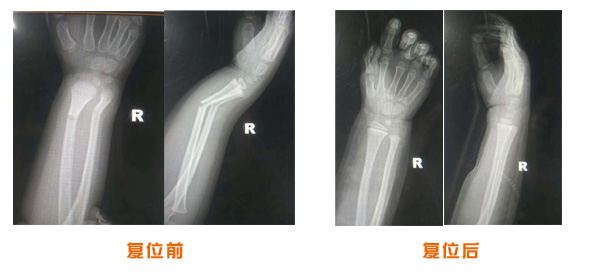

復位前后對比